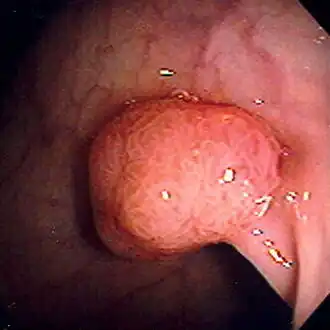

![]() Полип аденоматозной структуры сигмовидной кишки, выявленный во время колоноскопии. Диаметр около 1 см. Удалён диатермической петлей | |

Полип толстой кишки, или колоректальный полип, — это полип (нарост), образующийся на внутренней поверхности ободочной или прямой кишок. Полипы толстой кишки обычно не ассоциируются с какими-либо симптомами. Иногда могут становиться причиной выделения крови с калом. Полипы толстой кишки требуют повышенного внимания из-за вероятности наличия в них злокачественных сегментов и риска перерождения доброкачественных полипов толстой кишки (аденом) через некоторое время в злокачественные новообразования.

Так как большинство полипов не вызывают каких-либо симптомов, то их, как правило, обнаруживают во время медицинского обследования: ректороманоскопии, колоноскопии, ирригоскопии.

По установившейся практике обнаруженные полипы размером до 5 мм удаляются во время колоноскопии при помощи щипцов или петли. В случае, если во время ректороманоскопии или во время какой-либо другой диагностической процедуры были обнаружены аденоматозные полипы, то пациенту придётся пройти и процедуру колоноскопии с последующим удалением аденом в условиях хирургического стационара. Несмотря на то что злокачественные сегменты, как правило, не выявляются в полипах размером менее 2,5 см, удалению подлежат все обнаруженные аденоматозные полипы, чтобы снизить в будущем вероятность образования рака толстой кишки.